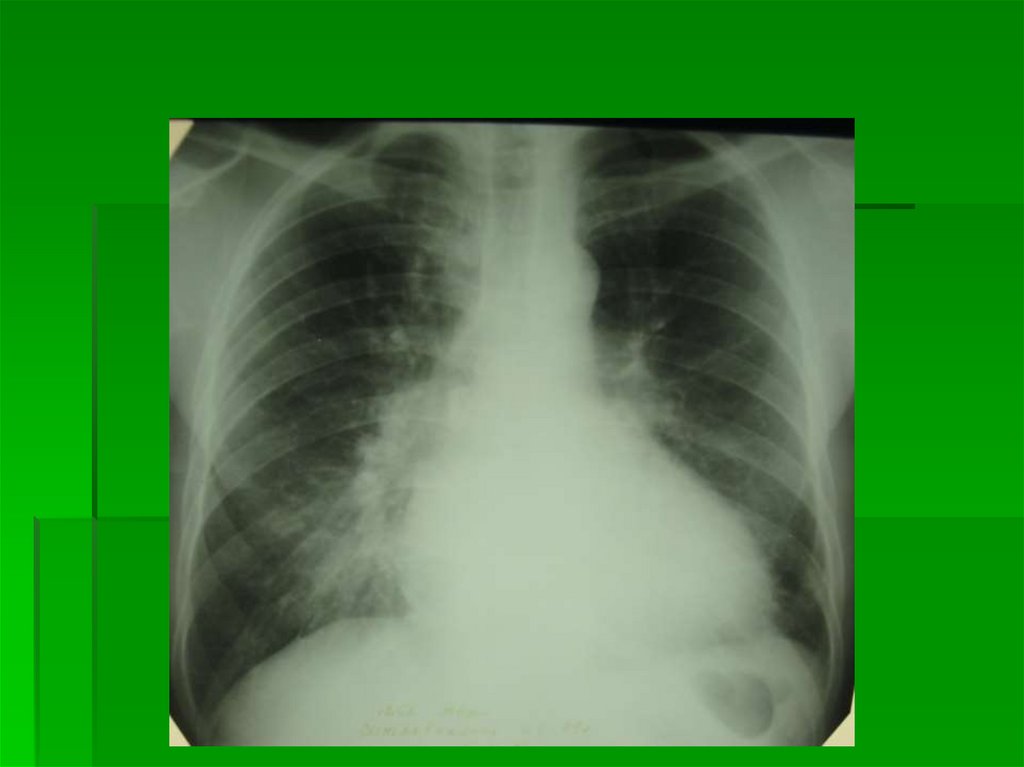

1 степень

Перераспределение кровотока

в МКК

P = 10-15 мм рт.ст.

Синонимы: Инверсия кровотока,

верхнедолевой застой, компенсированная

ЛВГ

Количество и коллибр сосудов в верхних

легочных полях больше, чем в нижних (3:1,

2:1, 1:1)

Проксимально сосуды прослеживаются до I

ребра, I межреберья, иногда доходят до

верхушки легких

Сосуды верхних легочных полей

располагаются параллельно срединной

тени

12.

В прикорневых зонах увеличено количество

сосудов в ортогональной проекции

В базальных отделах легких сосуды

спазмированы (защитный механизм), не

прослеживаются

Все видимые сосуды имеют четкий

наружный контур

Головка корня выделяется по сравнению с

центральной частью